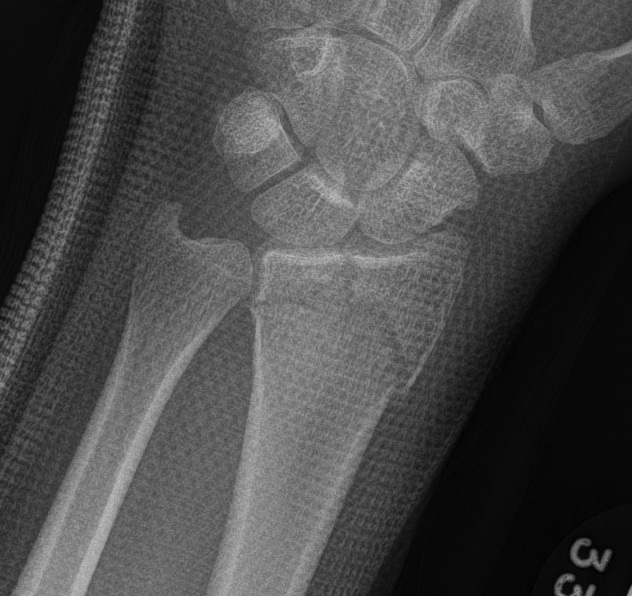

DRDR

Dr shortDR short

Distal radius fracture with shortening and dorsal tilt